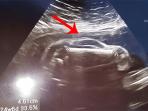

Hasil USG, Janin Mirip Mobil Sport

Foto hasil USG yang diunggah seorang calon ayah mendadak menjadi pembicaraan di media sosial